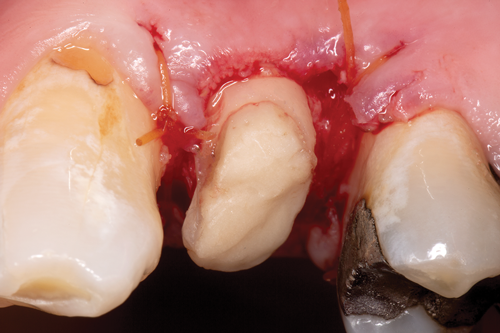

After completion of the endodontic treatment and crown lengthening to develop an ideal ferrule effect (Figure 3 through Figure 5) a diagnostic wax-up was fabricated to an ideal coronal preparation geometric shape, dimension, and height for the anticipated final composite core buildup (Figure 6). A clear polyvinyl siloxane (PVS) impression material was injected into a nonperforated tray, placed over the diagnostic wax-up, and then put into a pressure pot with cold water for 5 minutes. This procedure is aimed at reducing the potential for the formation of voids and bubbles in the impression material (Figure 7 and Figure 8). A small opening was made above the tooth to be restored using a tapered diamond bur (6847) (Figure 9). It is important to clean the internal surfaces with a microbrush to prevent silicone debris from integrating into the flowable material. Prior to the restorative procedure, a diagnostic wax-up was fabricated to the anticipated extracoronal contours for development of the final crown (Figure 10).

After determination of the desired post channel length (one-half to two-thirds the length of the canal), a dental dam was placed using the modified dam technique. The gutta-percha was removed with a series of preshaping instruments (Gates Glidden drills). The channel preparation for a prefabricated fiber-reinforced post (ie, the fiber-optic post system referred to earlier) was performed using a color-coded drill from this post system, establishing the desired intraradicular length and size for the selected post (Figure 11). The prepared channel was rinsed with water and dried with an endodontic paper point.

Fig 3. After endodontic treatment, crown lengthening was performed to develop an ideal ferrule effect.

Figure 3

Fig 4. An adequate collar effect of 2 mm of sound tooth structure would provide an anti-rotational feature for the stability of the crown.

Figure 4

Fig 5. Buccal view of optimal ferrule effect with a healthy biological framework.

Figure 5